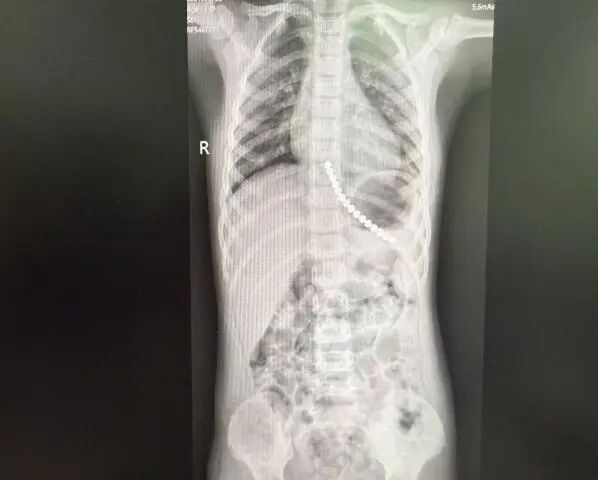

就在次日

该院又接收1例

因误吞铁钉而实施内镜下取物的

1岁幼儿

阜阳市妇女儿童医院小儿外科主任尚克磊表示“节假日是儿童误吞异物的高发期。磁珠、电池、铁钉等异物尤其危险必须在黄金时间内取出,否则可能导致严重并发症。”

医生会通过相关检查确定异物位置,再根据异物的性质和位置,选择安全、合适、有效的治疗方案。随着内镜技术的发展,约90%的上消化道异物可通过内镜微创取出。